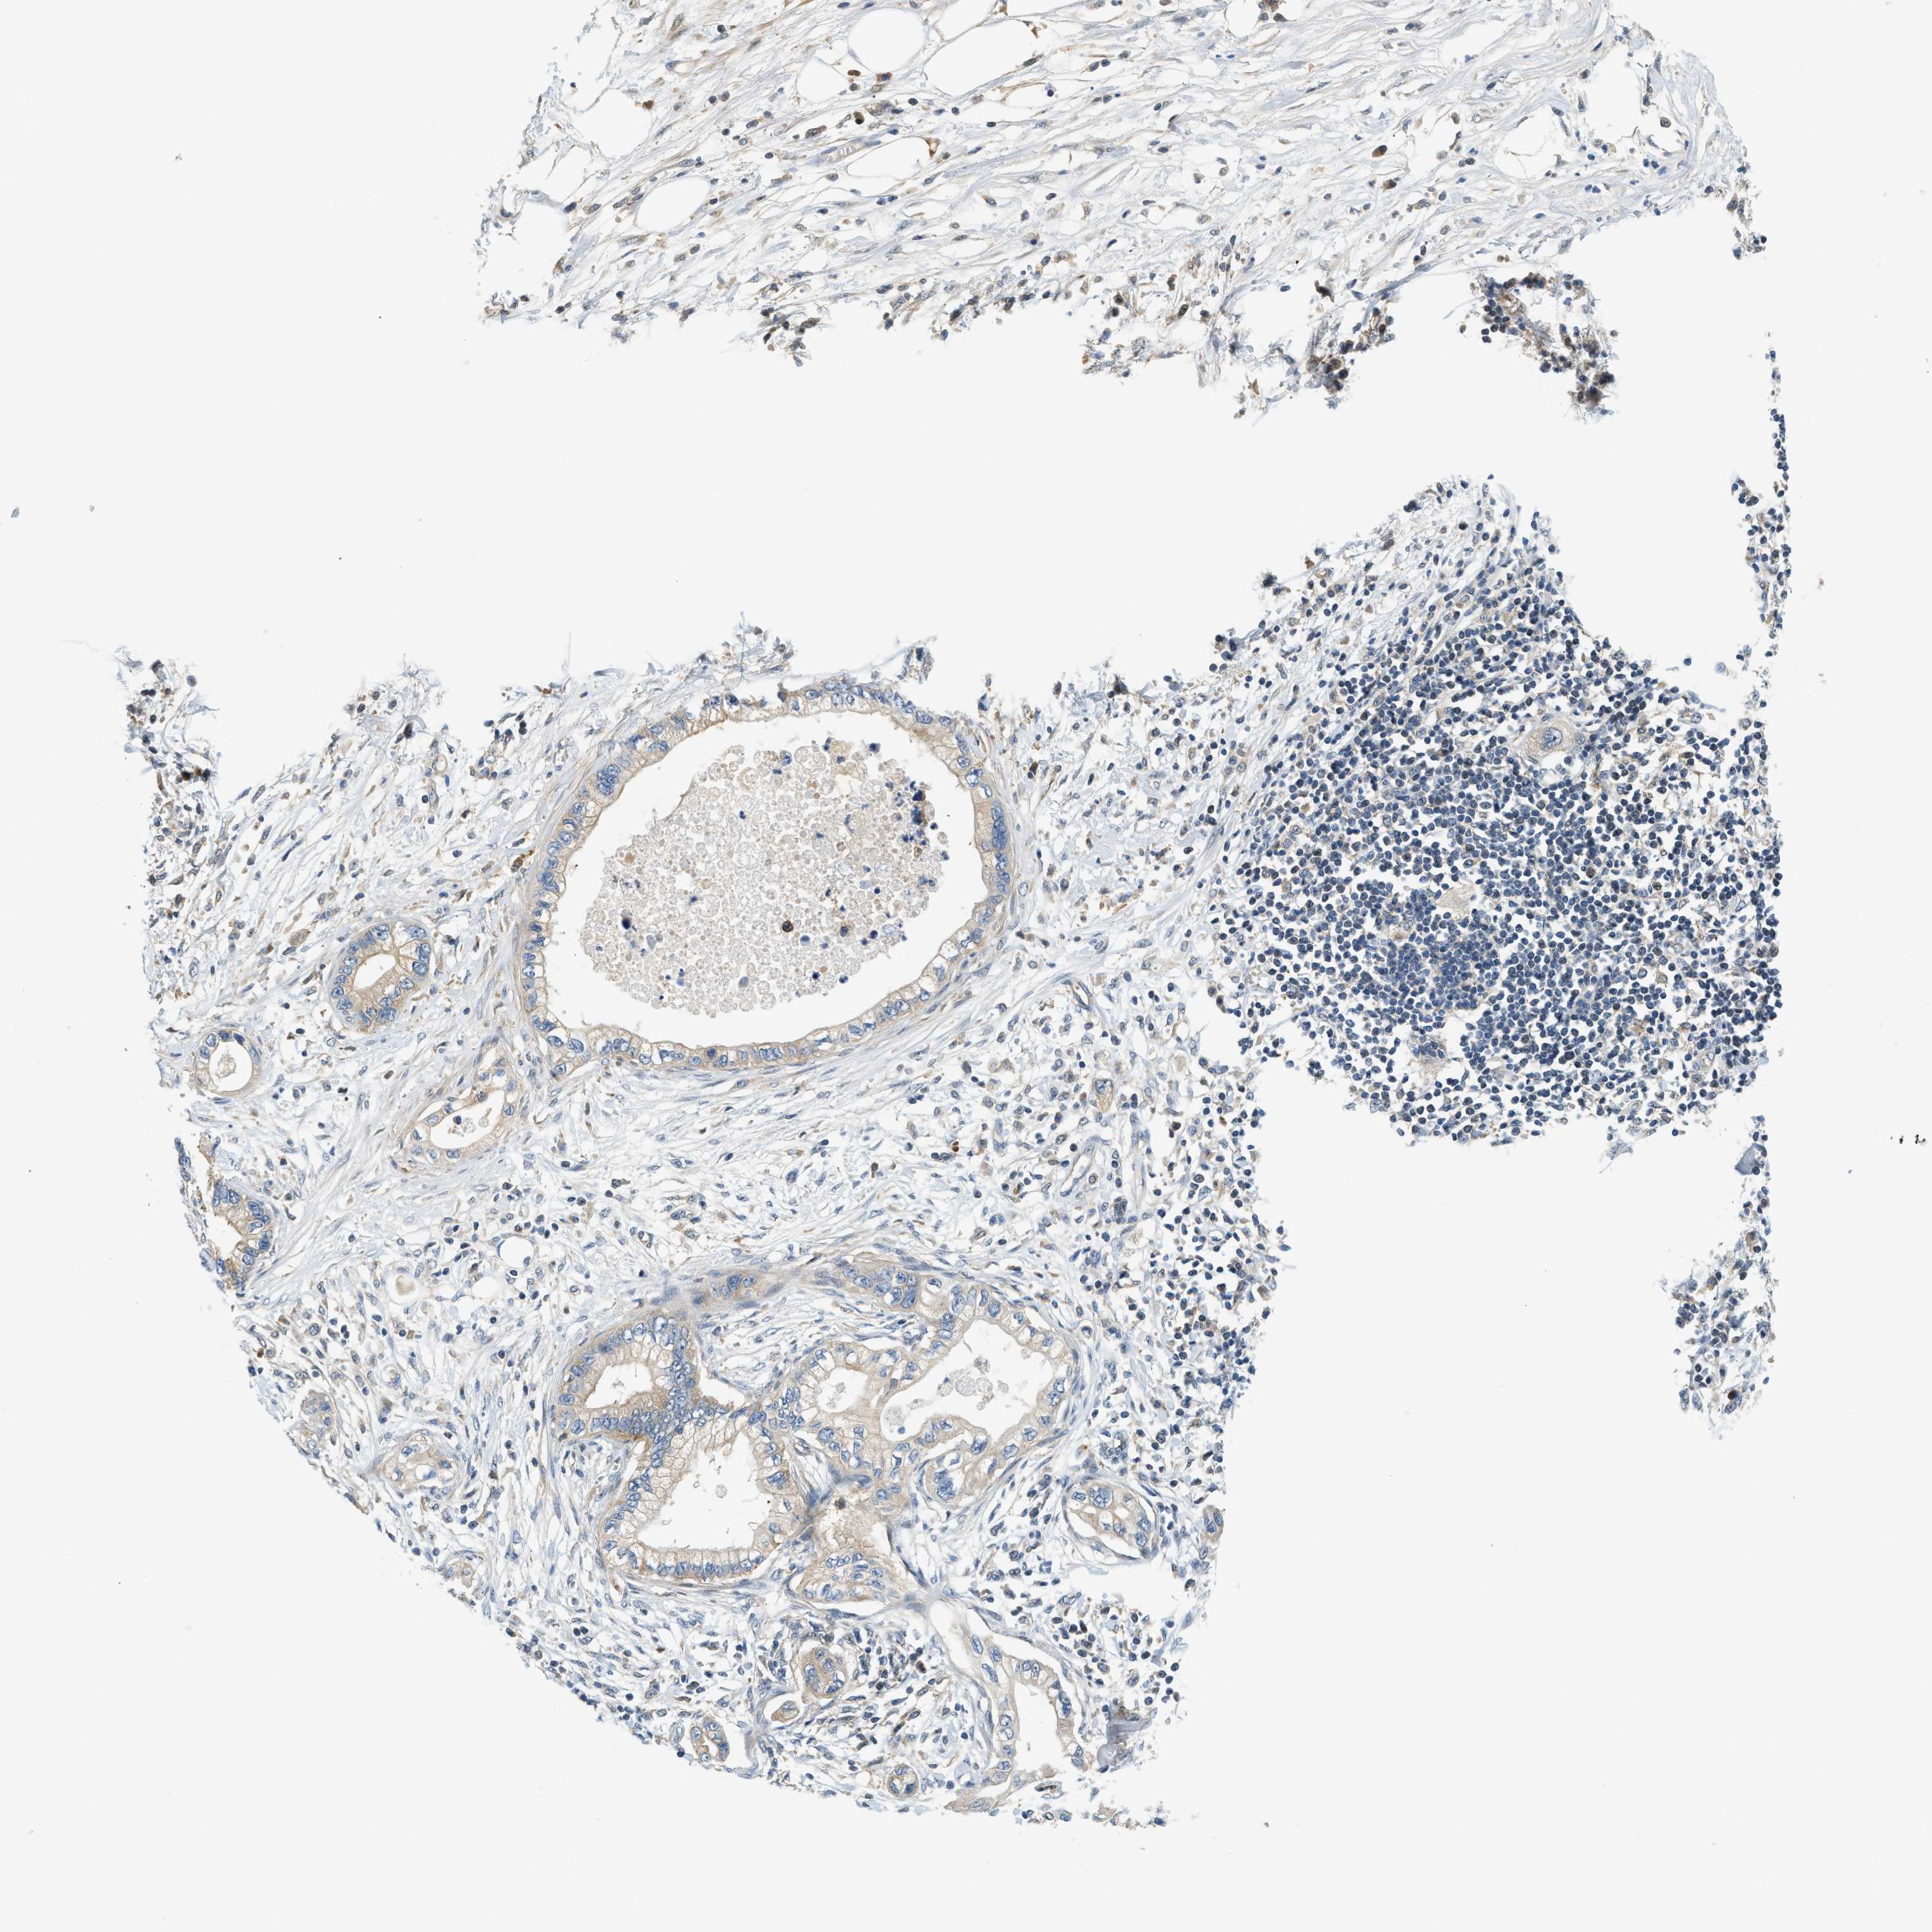

PANCREATIC CANCER - Protein expressioni

A mouse-over function shows sample information and annotation data. Click on an image to view it in a full screen mode. Samples can be filtered based on level of antibody staining by selecting one or several of the following categories: high, medium, low and not detected. The assay and annotation is described here.

Note that samples used for immunohistochemistry by the Human Protein Atlas do not correspond to samples in the TCGA dataset.

Antibody stainingi

Antibody staining in the annotated cell types in the current human tissue is reported as not detected, low, medium, or high, based on conventional immunohistochemistry profiling in selected tissues. This score is based on the combination of the staining intensity and fraction of stained cells.

Each image is clickable and will lead to virtual microscopy that enables deeper exploration of all samples and also displays staining intensity scores, fraction scores and subcellular localization as well as patient and tissue information for each sample.

Antibody HPA016049

Antibody CAB022588

Staining

High

Medium

Low

Not detected

Intensity

Strong

Moderate

Weak

Negative

Quantity

>75%

75%-25%

<25%

None

Location

Nuclear

Cytoplasmic/membranous

Cytoplasmic/membranous,nuclear

Adenocarcinoma, NOS

Adenocarcinoma, metastatic, NOS